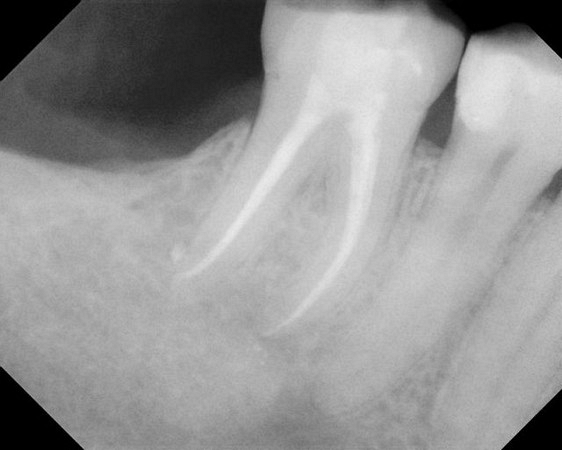

Here are examples of digital dental radiography